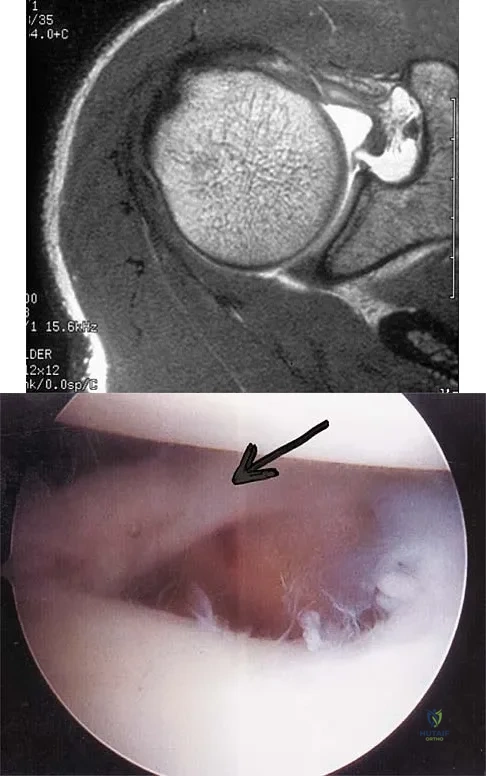

A 47-year-old male tennis player has pain in his nondominant shoulder that has failed to respond to 4 months of nonsurgical management. Examination reveals acromial tenderness and pain at the supraspinatus tendon insertion. He has a positive impingement sign, pain on forward elevation, and minimal cuff weakness. The MRI scans are shown in Figures 30a and 30b. To completely resolve his symptoms, treatment should consist of

A patient has right shoulder pain. Figure 1a shows a gadolinium-enhanced transverse MRI scan at the level of the coracoid. Figure 1b shows an arthroscopic view of the anterior structures from a posterior portal. These images reveal which of the following findings?